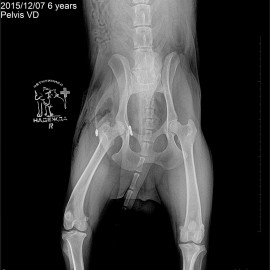

После автотравмы перестал вставать на заднюю правую лапу. После проведенных обследований был поставлен диагноз - вывих правого тазобедренного сустава. Была проведена операция: остеосинтез правого тазобедренного сустава. При операции для стабилизации сустава установлен протез круглой связки.

Снимок 2 после операции.